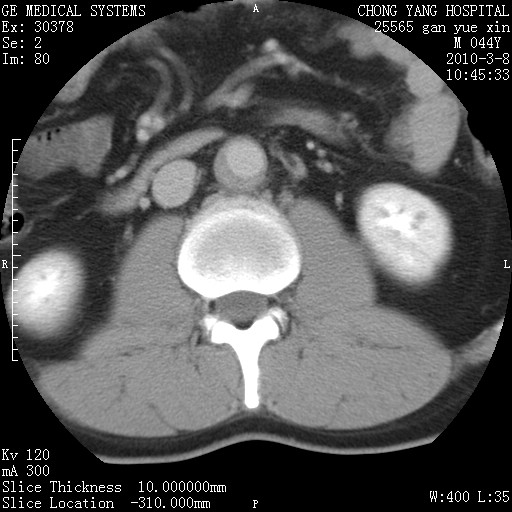

标题: CT24940:主动脉增强,典型病例。 [打印本页]

标题: CT24940:主动脉增强,典型病例。

夹层动脉瘤。

动脉夹层

夹层动脉瘤,典型

主动脉夹层。

动脉夹层的分型:

⒈debakey分型:根据主动脉夹层累及部位,分为三型:ⅰ型:原发破口位于升主动脉或主动脉弓部,夹层累及升主动脉、主动脉弓部、胸主动脉、腹主动脉大部或全部,少数可累及髂动脉。ⅱ型:原发破口位于升主动脉,夹层累及升主动脉,少数可累及部分主动脉弓。ⅲ型:原发破口位于左锁骨下动脉开口远端,根据夹层累及范围又分为ⅲa,ⅲb。ⅲa型:夹层累及胸主动脉。ⅲb型:夹层累及升主动脉、腹主动脉大部或全部。少数可累及髂动脉。

⒉stanford分型:a型:夹层累及升主动脉,无论远端范围如何。b型:夹层累及左锁骨下动脉开口以远的降主动脉。

夹层动脉瘤,少量胸水

夹层动脉瘤;左侧少量胸腔积液。

典型主动脉夹层。